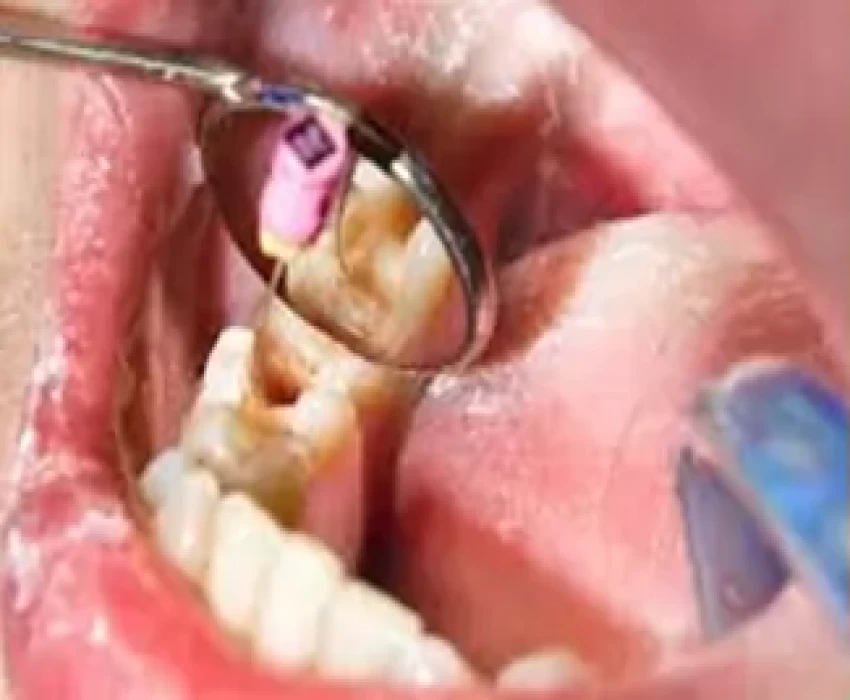

Despite the dental profession's emphasis on prevention, threats to pulp survival, such as caries, restorative dental treatment, and traumatic injuries, have not been eliminated. As a consequence, children continue to lose teeth prematurely, and procedures aimed at preventing and treating pulp disease in the primary and immature permanent dentitions remain an integral part of contemporary dental practice. Some may question why efforts to preserve pulpally involved primary teeth are important. These practitioners maintain that such efforts may present a risk to developing permanent successors and, in any case, the primary teeth will be lost before long. Preservation of arch space is one of the principal objectives of pediatric dentistry. Premature loss of primary teeth may cause aberration of the arch length, resulting in mesial drift of the permanent teeth and consequent malocclusion. Whenever possible, the tooth with pulp involvement should be maintained within the dental arch in a functional and disease-free condition. Other objectives of preserving the primary teeth are to safeguard aesthetics and mastication, prevent aberrant tongue habits, aid in speech, and prevent the psychological effects that may be associated with tooth loss. Premature loss of the maxillary incisors before 3 years of age has been shown to cause speech impairment that may persist in later years.

It is equally undesirable for children to suffer the unplanned loss of permanent teeth, and it should be noted that the prognosis for lifelong retention of an immature tooth with a short root and fragile dentinal walls is far worse than for a mature permanent tooth. Special treatments for the immature permanent tooth, therefore, focus on preserving vital pulp functions, at least until dental development is complete